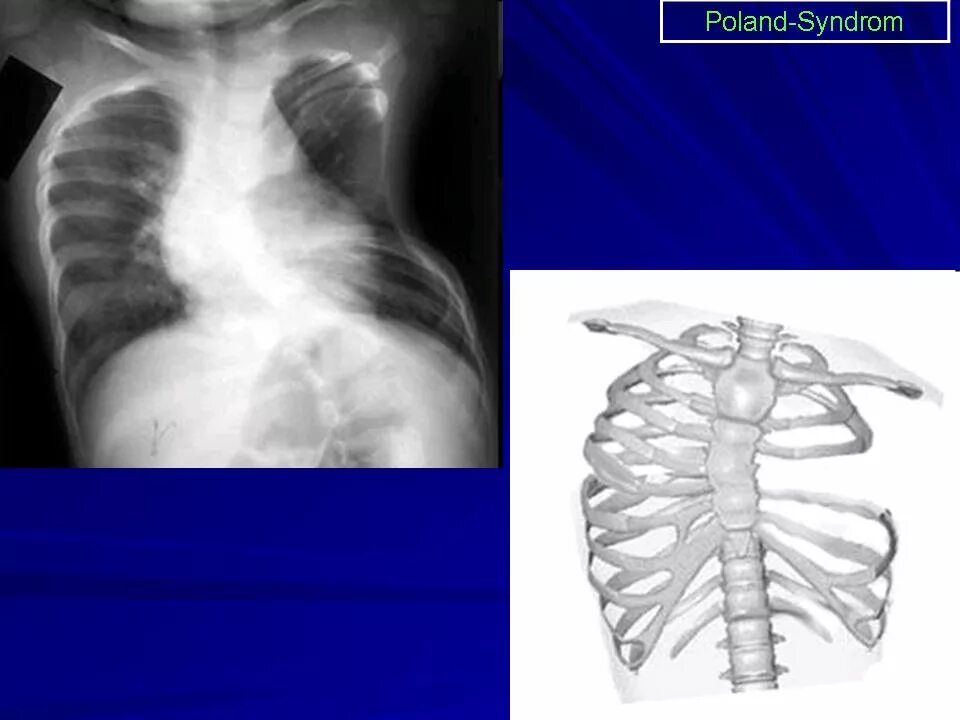

Гипоплазия 12 пары ребер